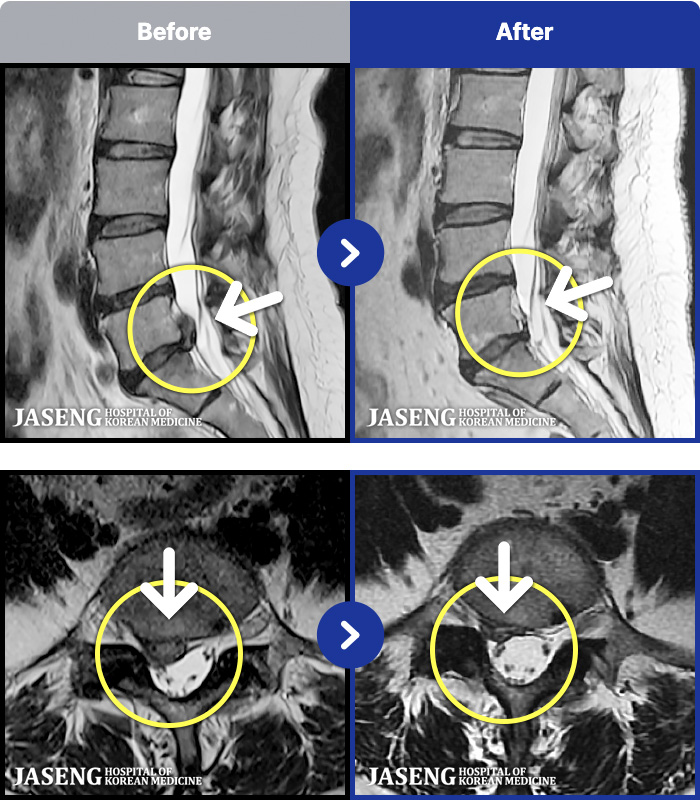

103 MRI ũ ʸ Ȯϼ.

ȯںп Ǹ ǿ ԿǾ, ο ġ ۿ Ƿ ġḦ Ͻñ ٶϴ.